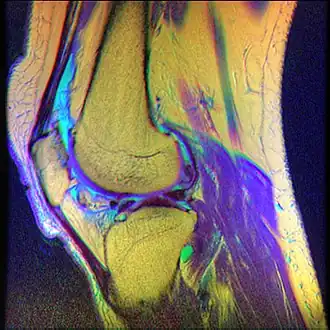

La condromalacia rotuliana también conocida como síndrome femoropatelar, condromalacia patelar o condritis rotuliana es una enfermedad caracterizada por la degeneración de la superficie articular cartílago que constituye la cápsula posterior de la rodilla. Produce malestar o dolor sordo alrededor o detrás de la rótula, y es un padecimiento bastante común entre adultos jóvenes, especialmente jugadores de baloncesto, vóley, fútbol, ciclistas, karatecas, tenistas, remeros, bailarines de ballet, corredores, etc. Los jugadores de rugby son también propensos a esta enfermedad, especialmente quienes juegan en posiciones en las que las rodillas realizan esfuerzos importantes. Asimismo, los alpinistas también son propensos a padecerla, al soportar un gran peso por sus mochilas y sobre todo en nieve.

Puede generarse a partir de una lesión aguda de la rótula o mediante la fricción crónica entre la rótula y la articulación del fémur al mover la rodilla. El diagnóstico de condromalacia corresponde a una rodilla cuya estructura ha sido dañada, mientras que la descripción más genérica de "síndrome patelo-femoral" se refiere a los estadios iniciales de la enfermedad, en los que los síntomas pueden ser totalmente reversibles.